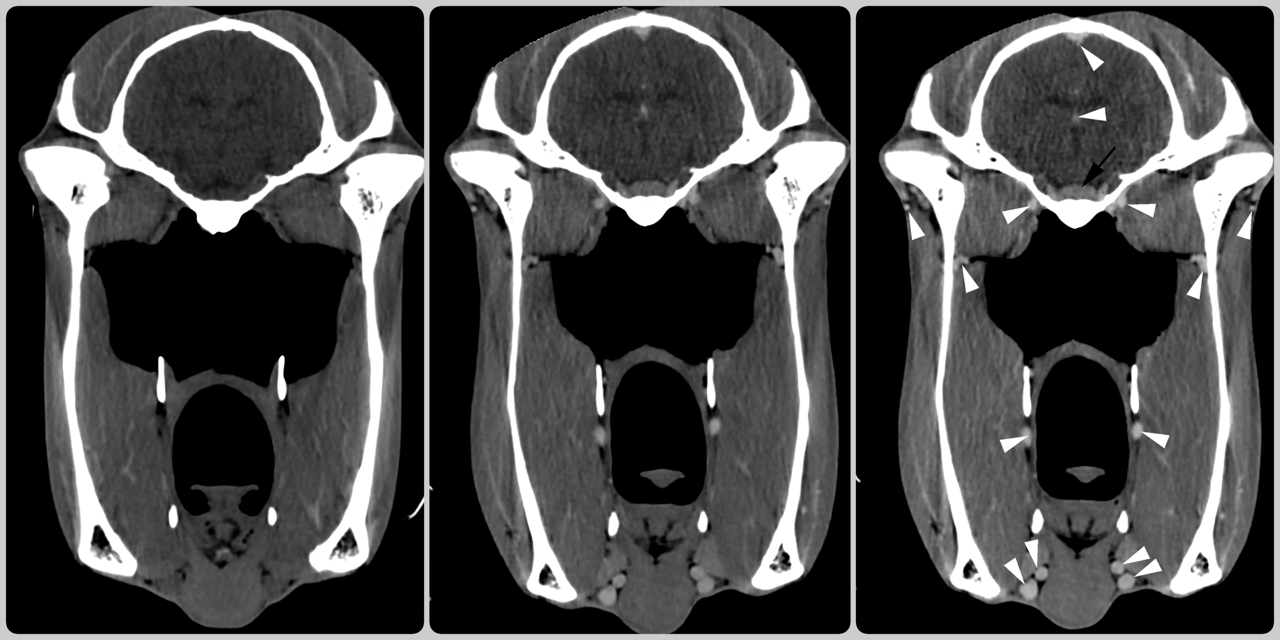

Same horse, same day ... so what have we done to make the CT scan on the left (image 1) look different from the middle one (image 2)?

We have injected contrast into the veins which we can see highlighting the blood vessels (white arrow heads) and the pituitary gland (black arrow) at the base of the brain (image 3).

Contrast enhanced CT is useful for assessing regions of increased or decreased blood flow or leaking blood vessels. This helps us identify soft tissue lesions and infectious or inflammatory processes. The use of contrast enhanced CT imaging is a huge asset to us at BELL EQUINE to improve diagnosis using our state-of-the-art CT scanner and can be performed in standing horses.

(Image 1: pre-contrast; image 2: post contrast; image 3: marked up image showing contrast uptake)